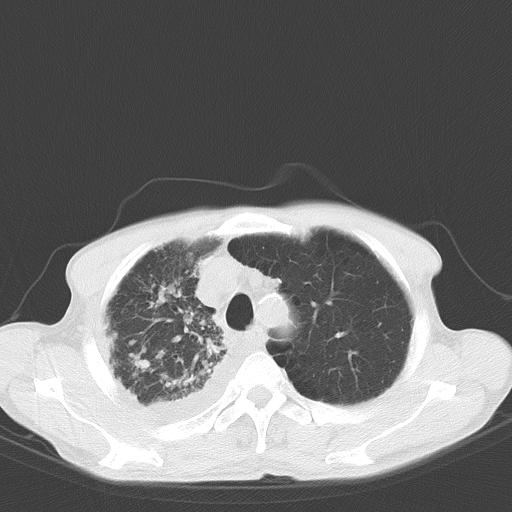

男性 75  咳嗽 一周前发热最高达39

右肺继发型tb并右侧tb性胸腔炎,右侧胸腔大量积液并右下肺膨胀不全,慢支肺气肿、多发肺大泡。建议抽胸水实验室检查并复查排除恶性在占位。

右上肺继发型肺结核,右胸腔中等量积液。

结核的基础上有纵隔淋巴结肿大,右侧有胸水,但右侧纵隔反而窄,说明有肺有不张。

再就是右下肺有块影,和不张混合,还是不能除外肺癌。

补充材料,患者2月份ct片大致正常,双侧胸腔积液,2月份抽胸水未发现ca细胞,现患者发热,痰多,各气管通畅,

1)右肺继发型肺结核。2)左肺胸膜下多发性肺大泡。3)右侧胸腔积液。